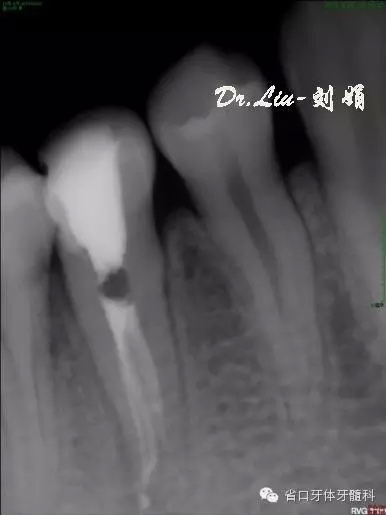

圖8:1月后復(fù)診根尖低密度影有消退趨勢

45橡皮障隔離下去封藥,清理根管,沖洗,紙尖干燥根管,拍攝試主尖片,顯微鏡下行熱牙膠根管充填,X線片顯示恰填。

圖10:根充后X線片